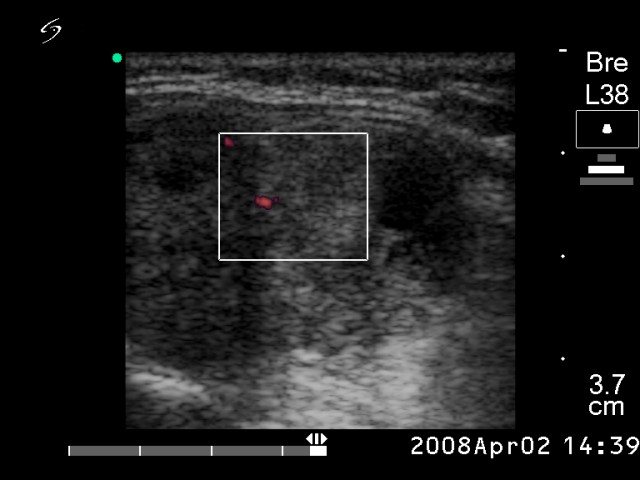

Lymph nodes - case conp 025

Six years prior to present examination (ultrasonographic picture 4)

Left lobe, longitudinal scan, power Doppler mode.